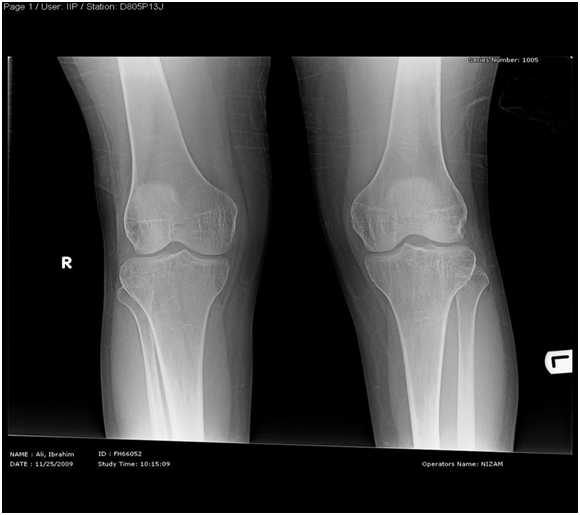

Skeletal X-Ray: 6 months later

- Pelvis & both Femori: there is thickening of secondary bone trabeculae ,in the neck and metaphysis of both femori indicating osteopenia

- Upper Limbs & legs: normal cortical thickness but there is also thickening of secondary bone trabeculae in the distal tibia and fibula

- No Looser’s zones were detected.